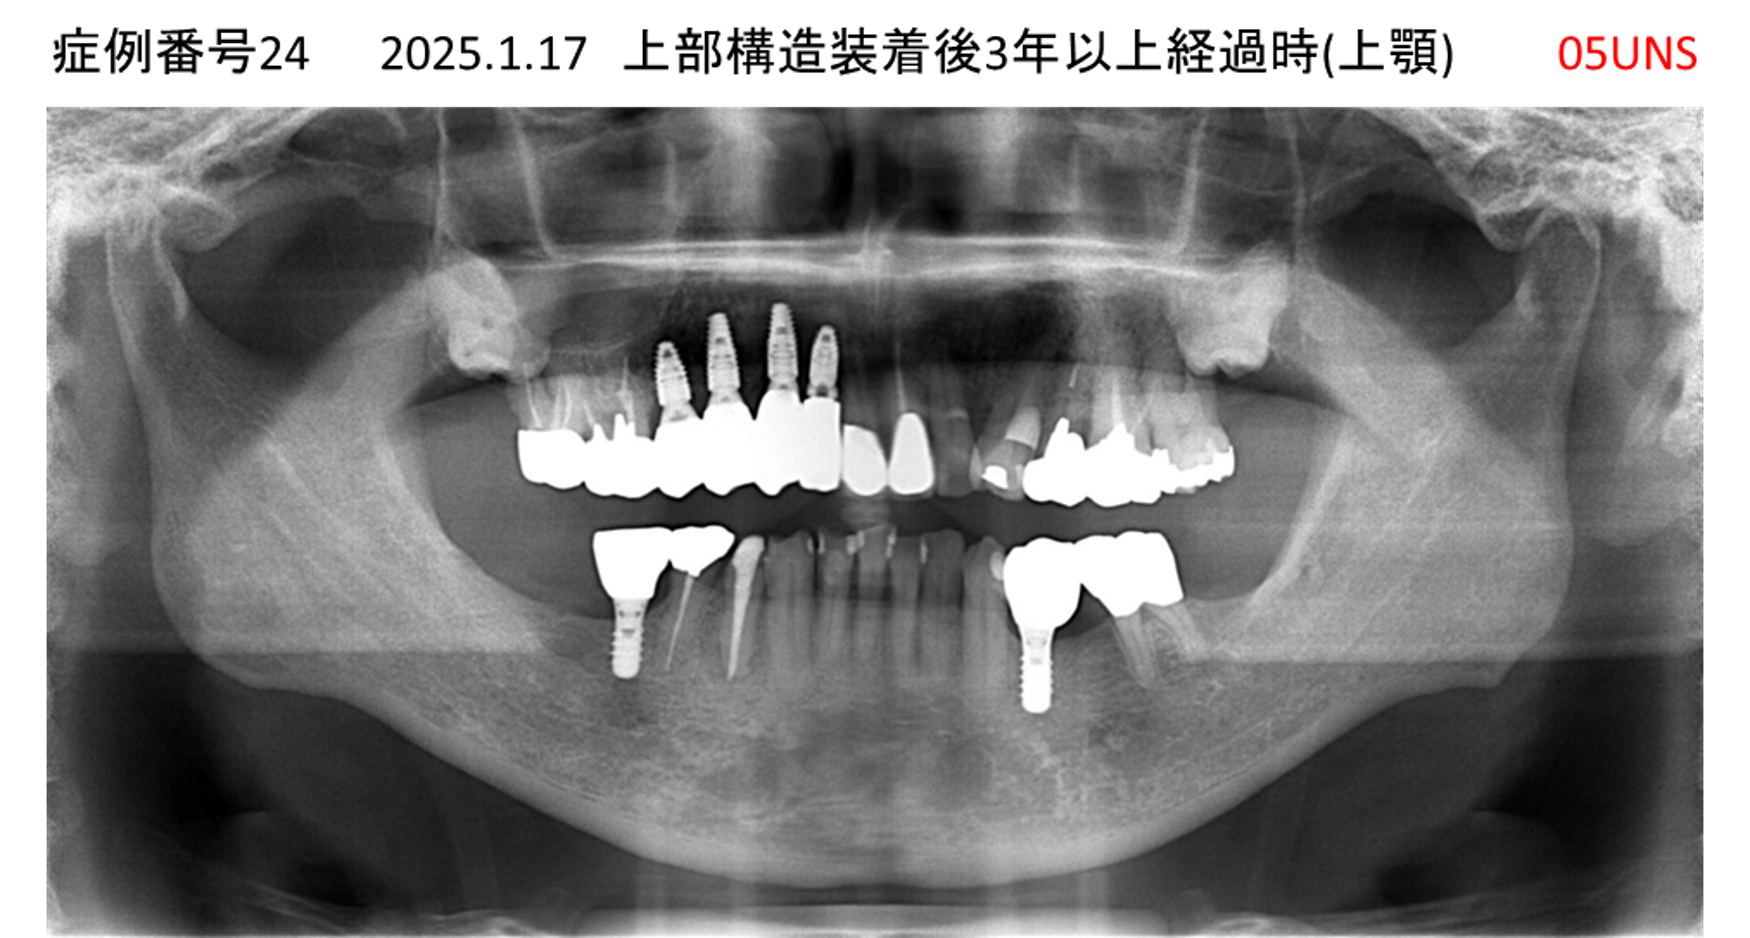

食事ができない/噛めない患者様のインプラント症例

| 治療名称 |

インプラント |

| 治療費用 |

540万円+税 |

| 治療期間 |

6か月 |

| 患者さんの症状(主訴) |

食事ができない。噛めない。上の前歯が揺れてきた。入れ歯がつらい。 |

| 治療内容 |

サイナスリフト、インプラント |

| 治療結果 |

なんでも食べられるようになった。力が入る(全身)ようになった。 |

| 治療の注意点(リスク/副作用) |

インプラントが壊れたら再治療が必要 |